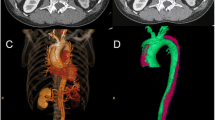

Sixteen male, healthy adult Beagles with body weights of 9–11 kg were housed separately at temperatures of 23–25 °C. They were fed in the West China Clinical Medical College of Sichuan University/The Experimental Animal Center of West China Hospital, following the regulations for experimental animal welfare. Canines were randomly divided into sham operation(SO) and dissection groups, and were subjected to median thoracotomy alone, or sternotomy with ascending aorta clamping and an aortic dissection surgical procedure, respectively,as previously reported [2]. Briefly, after routine sterile preparation and draping, a median sternotomy was performed to expose the ascending aorta. After the pericardium was elevated, the aortic wall was clamped at about 2 cm distal to the origin of the ascending aorta. A small round blade was used to cut across the adventitia and part of the media. The aortic clamp was loosened after the exposure of the medial space, followed by gentle and blunt extension of the medial space about 1 cm distally with the tip of a mosquito clamp, creating the initial false lumen. Then, the aortic wall was clamped again, and the remaining media and intima were excised, creating a communication between the false lumen and the aortic cavity. The torn intima was fixed with 6–0 Prolene to the opposite aortic wall, which helped the intima resist the force of blood flow and kept the false lumen open. After closure of the aortic wall to allow for continuous blood infusion into the false lumen, the wall clamp was carefully loosened. Finally, the chest wall was closed to finish the procedure, and the aortic dissection canine model was established. Animals in the SO group only underwent a median sternotomy, with no procedures on the aorta. Three-dimensional reconstruction images (Fig. 1a, b) and computed tomography in cross-sectional views (Fig. 1c, d) were used to demonstrate the AAD canine model.